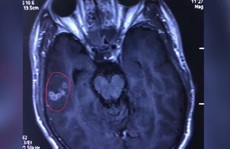

• Trung Quốc: Sán dây dài 10 cm chui vào não thanh niên mê đồ nướng

Trung Quốc: Sán dây dài 10 cm chui vào não thanh niên mê đồ nướng

(NLĐO) – Các bác sĩ ở Trung Quốc mới đây đã gắp một con sán dây dài 10 cm ra khỏi não một thanh niên thích ăn đồ nướng.

9/13/2018 9:28:27 AM